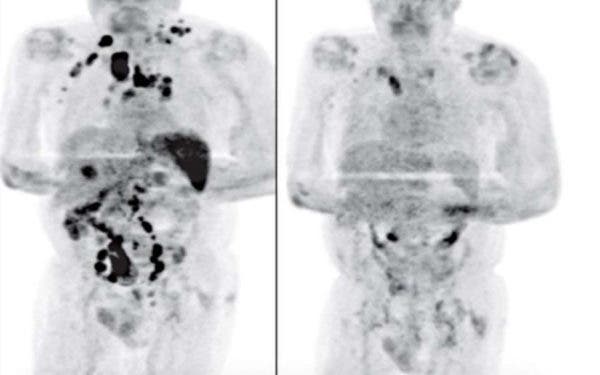

Mesmo com a gravidade do seu caso, o homem conseguiu vencer a doença. Após quatro meses de recuperação, o paciente percebeu que o inchaço dos nódulos do linfoma havia sido reduzido, o que foi confirmado através de um PET Scan (tomografia por emissão de pósitron), usado no diagnóstico do câncer.